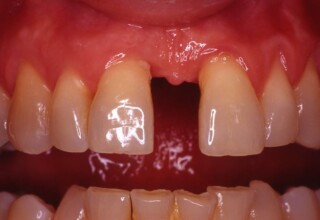

Τα απονευρωμένα δόντια πολλές φορές χάνουν την φωτεινότητα τους και σκουραίνουν σε αντιαισθητικό επίπεδο. Η λεύκανση τους προϋποθέτει άψογη απονεύρωση και υπομονή. Τοποθετείται ένα σφράγισμα στη ρίζα του δοντιού για να περιοριστεί η δράση του λευκαντικού υγρού μόνο στο τμήμα του δοντιού που είναι εμφανές στην στοματική κοιλότητα. Στην συνεχεία απαιτούνται 1-5 σύντομες συνεδρίες τοποθέτησης του λευκαντικού υλικού. Μετά τον αποχρωματισμό του δοντιού τοποθετείται ένα σφράγισμα ρητίνης με άψογη συγκόλληση για όσο το δυνατόν μακροχρόνια αποφυγή της μικροδιείσδυσης.

Αρχική εμφάνιση

Τελική εμφάνιση